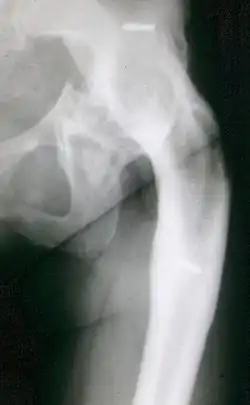

Der Begriff Arthrodese wurde von Eduard Albert eingeführt. Er nahm 1878 bei einem Mädchen mit Kinderlähmung die erste Arthrodese vor und erreichte standfeste Knie.[2] Im Jahr 1887 nahm er die erste erfolgreiche Hüftgelenksarthrodese vor. Der erste Bericht über eine erfolgreiche Hüftgelenksarthrodese aus dem französischen Sprachraum stammt aus dem Jahr 1886 von Lagrane, aus dem englischen von F. Albee 1908.[3]